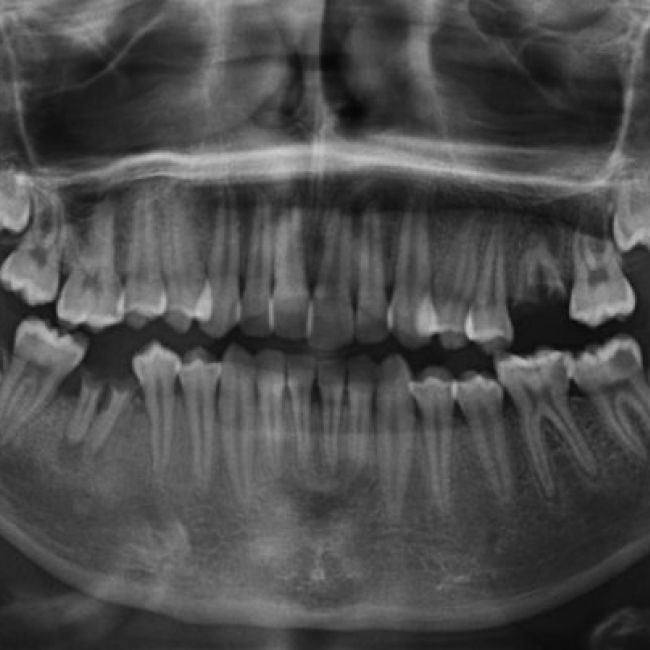

En los centros de Imagen Diagnóstica Dental Dr. Mayor ofrecemos una amplia variedad de servicios, gracias a la moderna aparatología con las que contanmos. Las pruebas diagnósticas que realizamos en nuestro centro son las siguientes: